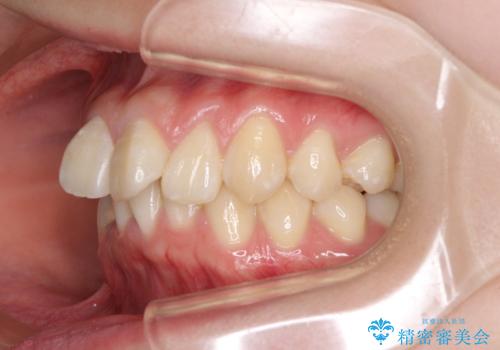

上下前歯の叢生をインビザラインできれいに

- 前歯のデコボコを気にして来院された患者様です。

前歯が重なっていることで口元が閉じにくくなっていたため、歯列全体の側方への拡大と、歯と歯の間を少し削ってスペースを獲得することとしました。